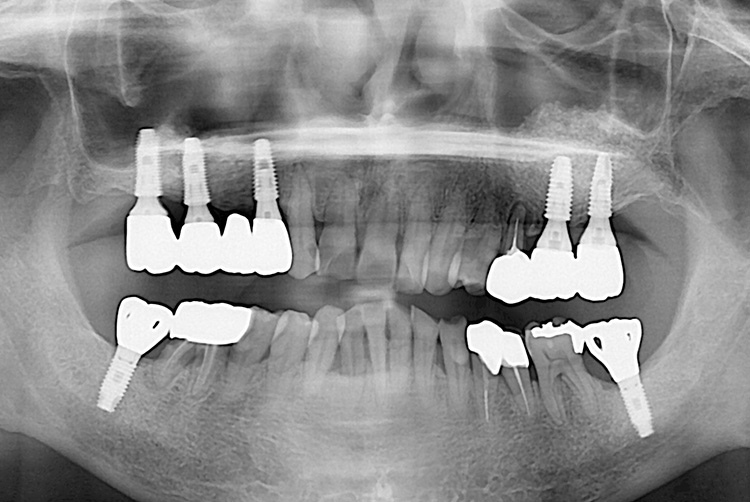

[임플란트] 임플란트

치료후 : 2019-09-24

세종치과는 많은 환자와 다양한 케이스를 바탕으로 항상 편안한 임플란트 수술을 제공하고자 노력하고,

오래동안 튼튼히 쓸 수 있는 임플란트 수술을 가장 큰 목표로 삼고 있습니다